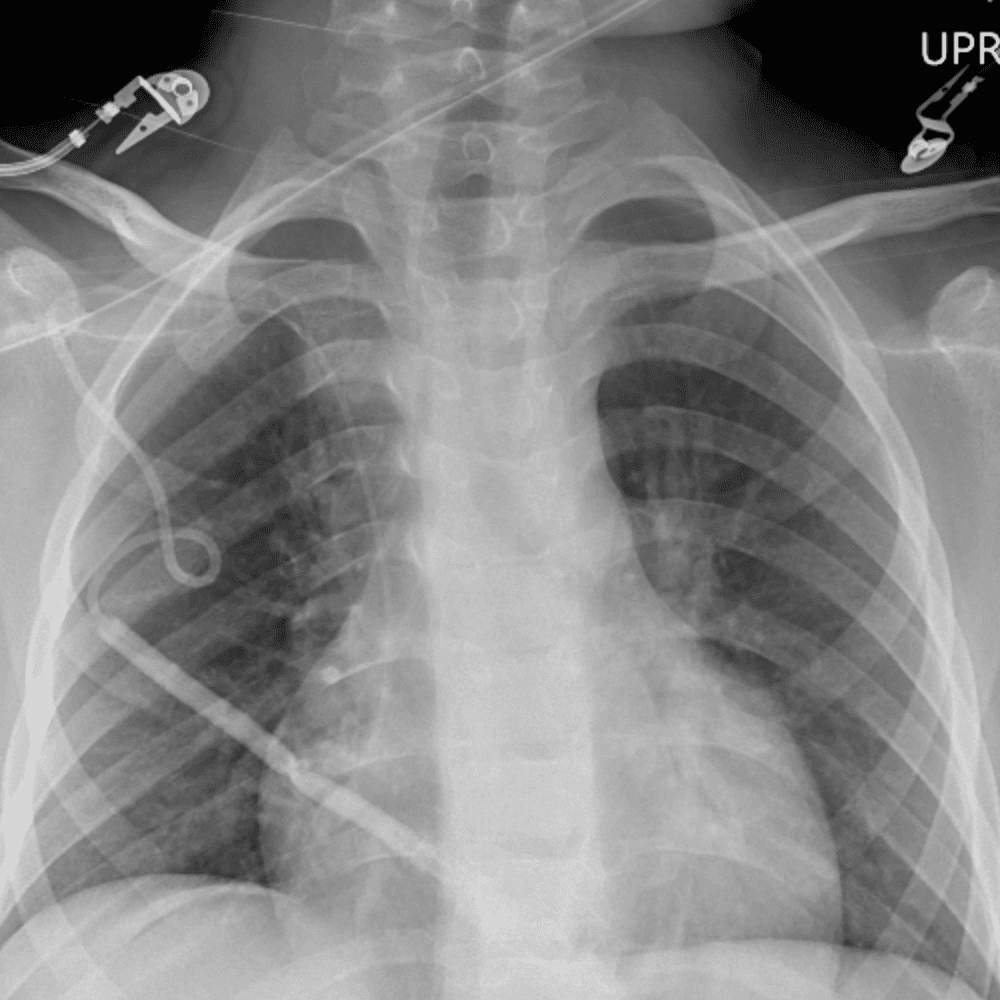

Peds Chest

Practice

Simulates call by including subtle or difficult cases and some normals.

50 cases